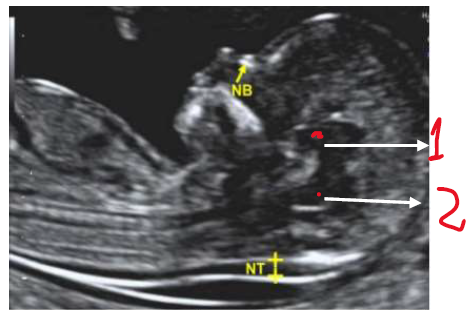

III - As estruturas assinaladas na imagem abaixo, correspondem ao diencéfalo (1) e ao tronco cerebral/ponte e bulbo (2).

IV - A imagem deve estar ampliada de maneira que apenas a cabeça e a parte superior do tórax sejam vistas.